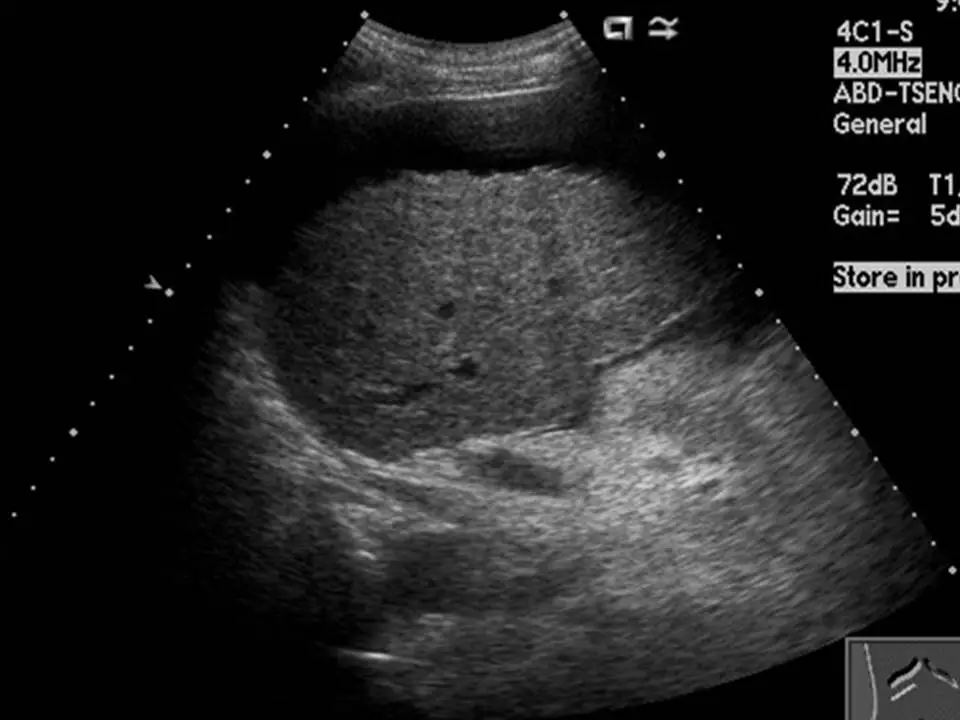

下圖之超音波影像中,最可能的診斷為下列何者?

本題超音波影像(探頭:4C1-S,頻率:4.0 MHz,腹部一般掃描)顯示以下特徵:

- 肝臟實質回音紋理:整體呈現明顯粗糙不均質的回音紋理(coarse heterogeneous echotexture),正常肝臟的均勻細緻回音結構已完全消失,代之以不規則的粗粒狀回音分布。

- 表面輪廓:肝臟表面不規則,可見輪廓凹凸不平,符合肝硬化表面結節化(surface nodularity)的特徵。

- 肝臟體積與形態:右葉有縮小傾向,整體肝臟輪廓失去正常圓弧形,邊緣較為鈍化。

- 血管結構:肝內血管(肝靜脈、門脈)邊界模糊,不如正常肝臟清晰可辨。

- 無明顯局灶性病灶:未見明確單一結節性病灶,排除局部結節性增生的典型表現。

上述影像特徵組合(粗糙不均質回音 + 表面不規則 + 右葉萎縮)高度提示肝硬化的診斷。